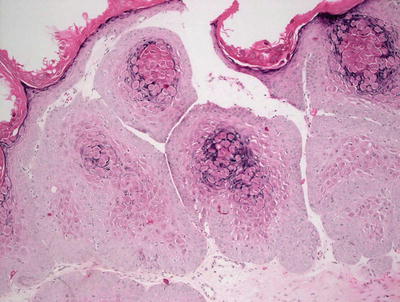

12.11.2 Histology

In verruca vulgaris, focal parakeratosis is present at the tips of exophytic papillomatous proliferations of the epidermis. The epidermis is acanthotic, and demonstrates hypergranulosis with focal clumping of keratohyalin granules (Figs. 12.16 and 12.17). In some cases, there is a slight pallor to the keratinocytes in the mid-portions of the epidermis. At low magnification, slight cup-shaped inward turning of the rete ridges at the periphery of the lesion may be apparent, and these features can be a useful diagnostic clue. There are dilated capillaries within the dermal papillae, and may result in foci of hemorrhage and thrombosis within the stratum corneum.

Fig. 12.16

Verruca vulgaris demonstrates an acanthotic and papillomatous epidermis

Fig. 12.17

Clumping of keratohyaline granules within the granular layer is characteristic of verruca vulgaris